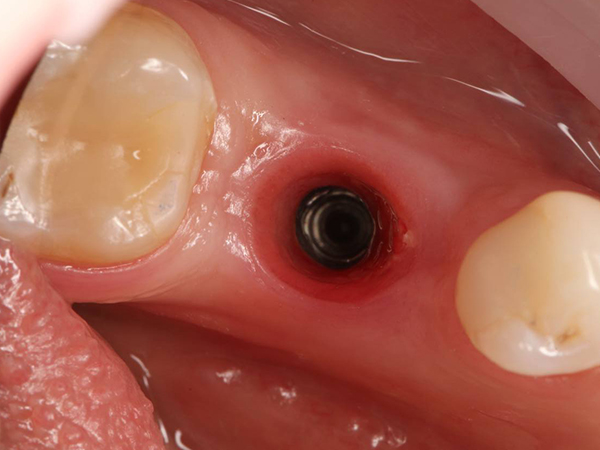

- финальный этап

После